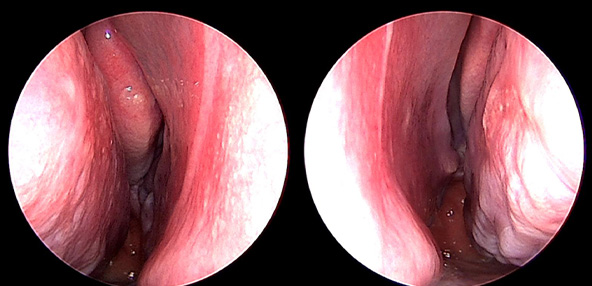

본 사진은 의료기관에서 진료를 본 환자이고, 전후 사진 인물이 동일인이며,동일조건에서 촬영이 되었습니다.